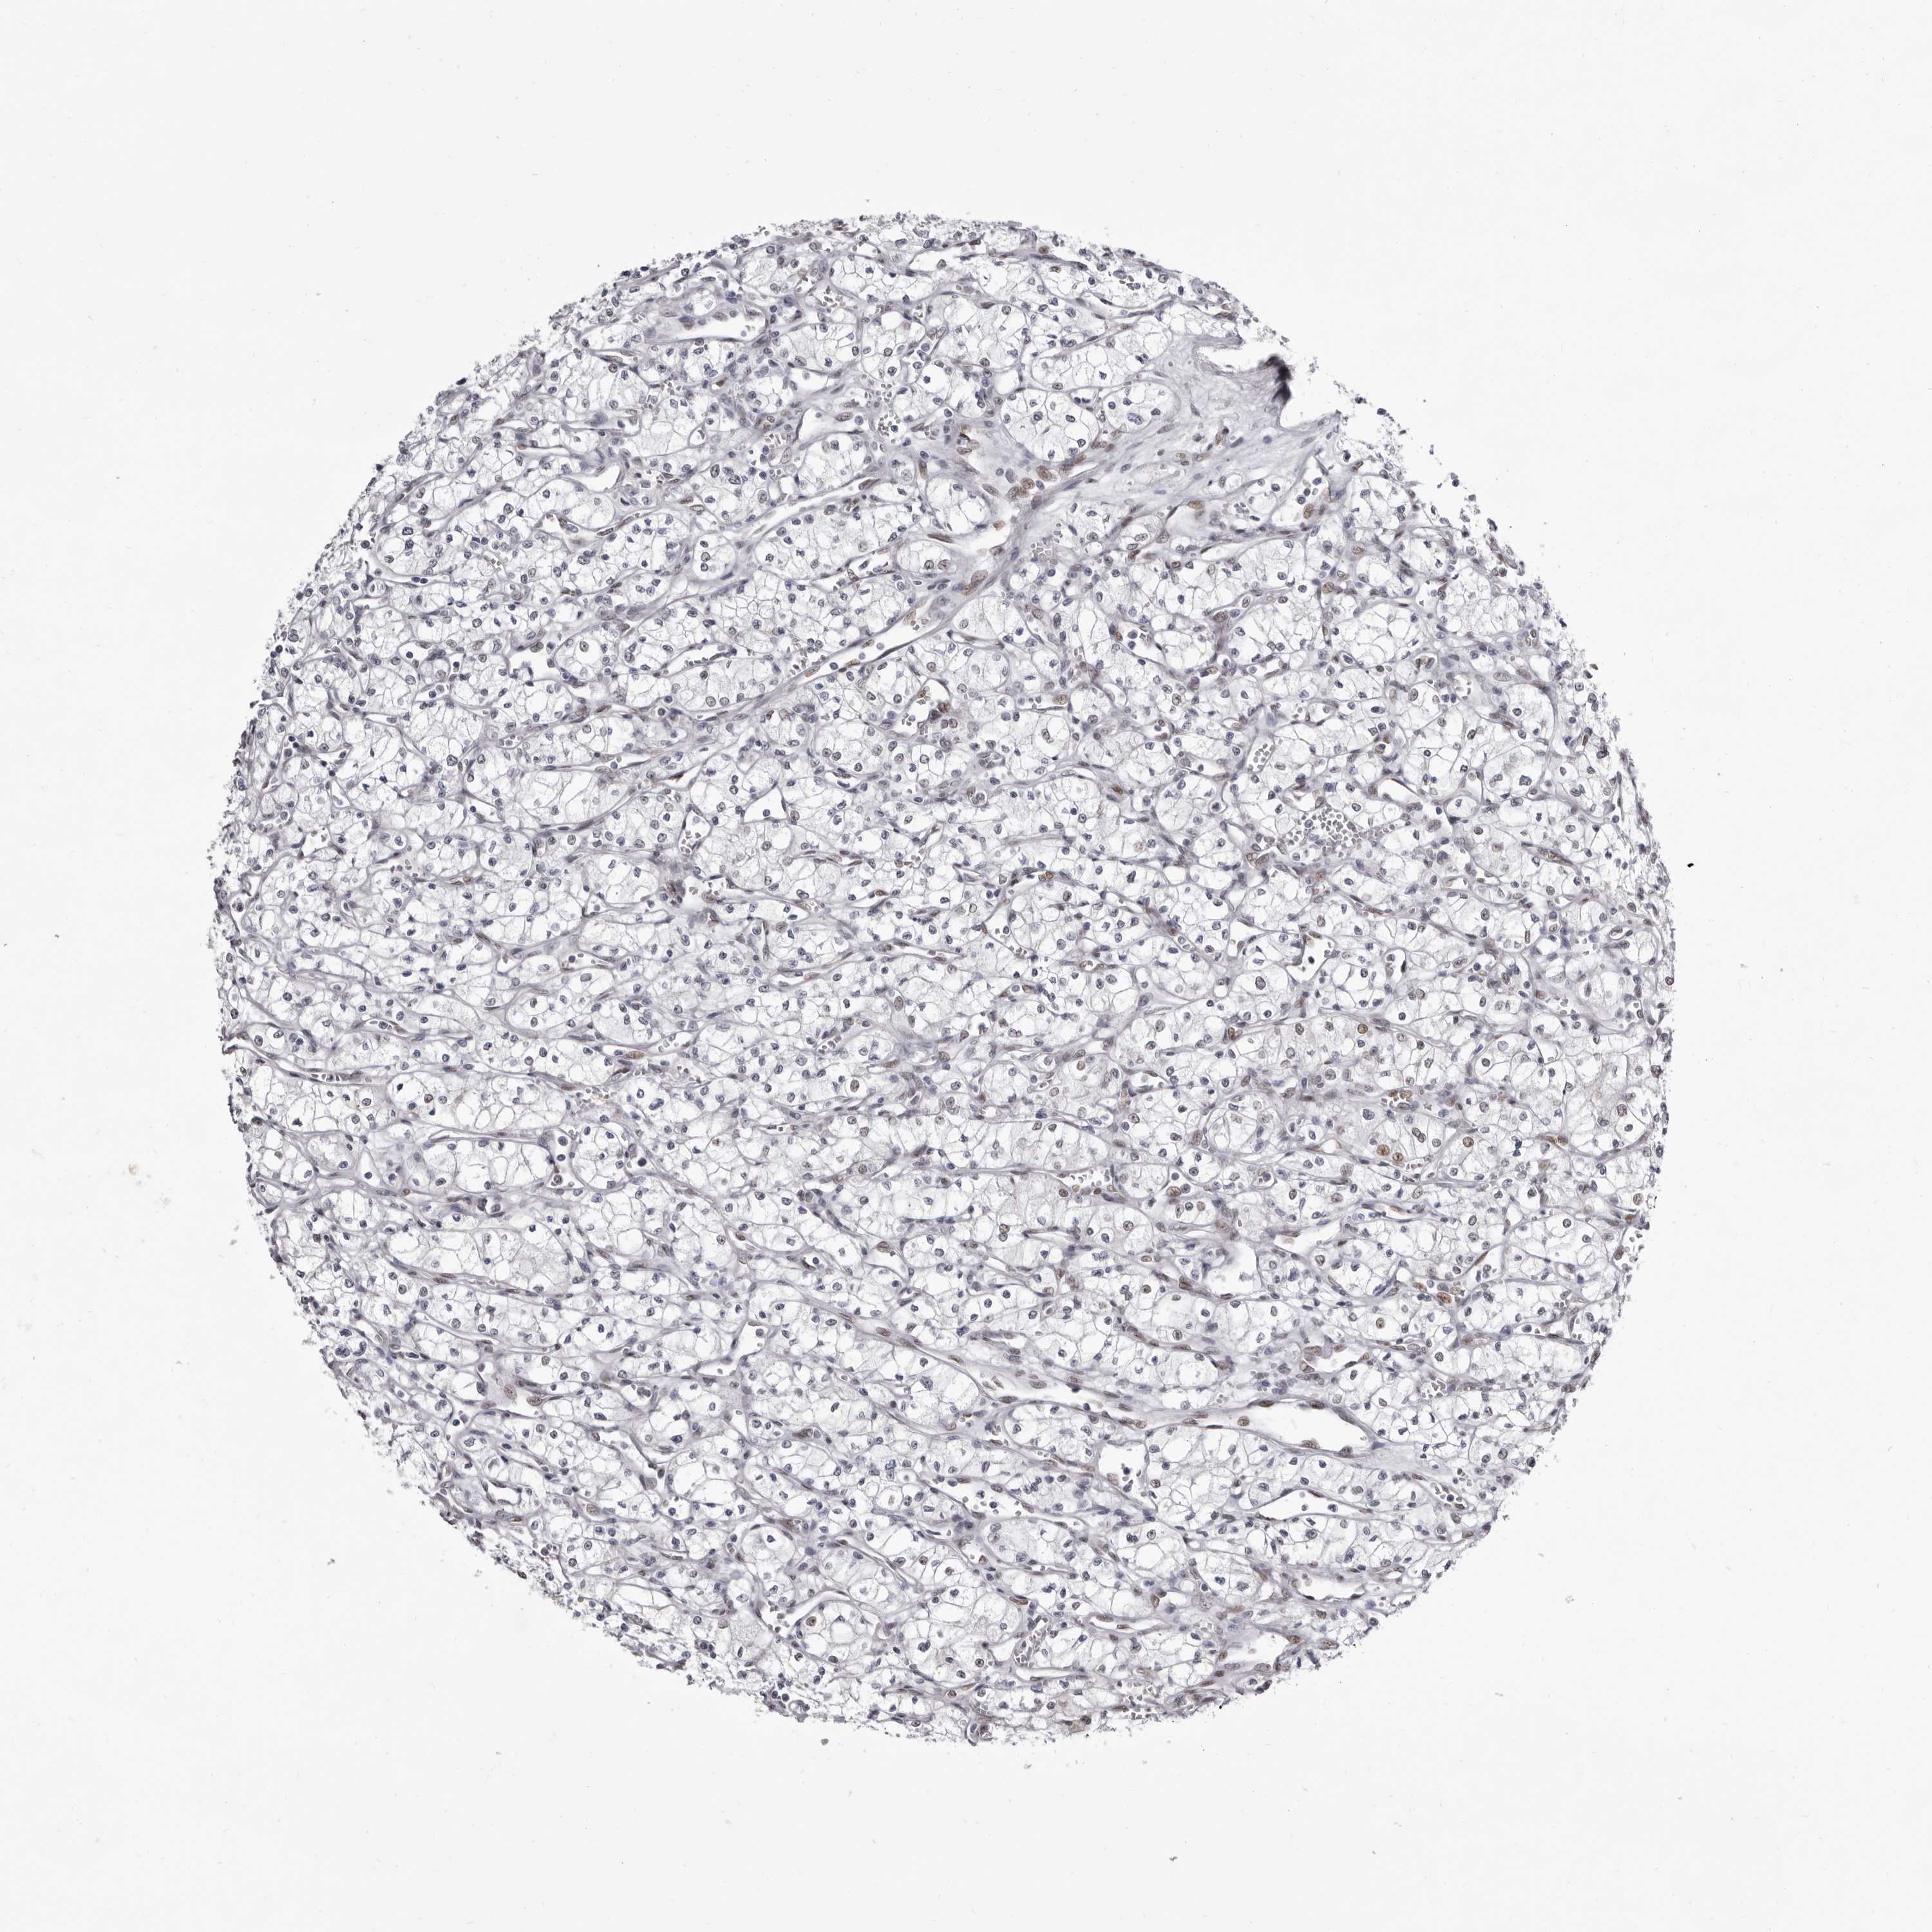

CANCER RENAL CANCER Show tissue menu

KICH TCGA KIRC TCGA KIRC VALIDATION KIRP TCGA PROTEIN RCC CPTAC PROTEIN EXPRESSION

KIDNEY RENAL PAPILLARY CELL CARCINOMA (TCGA) - Interactive survival scatter ploti

ZNF326 is not prognostic in Kidney Renal Papillary Cell Carcinoma (TCGA)

: 2.27